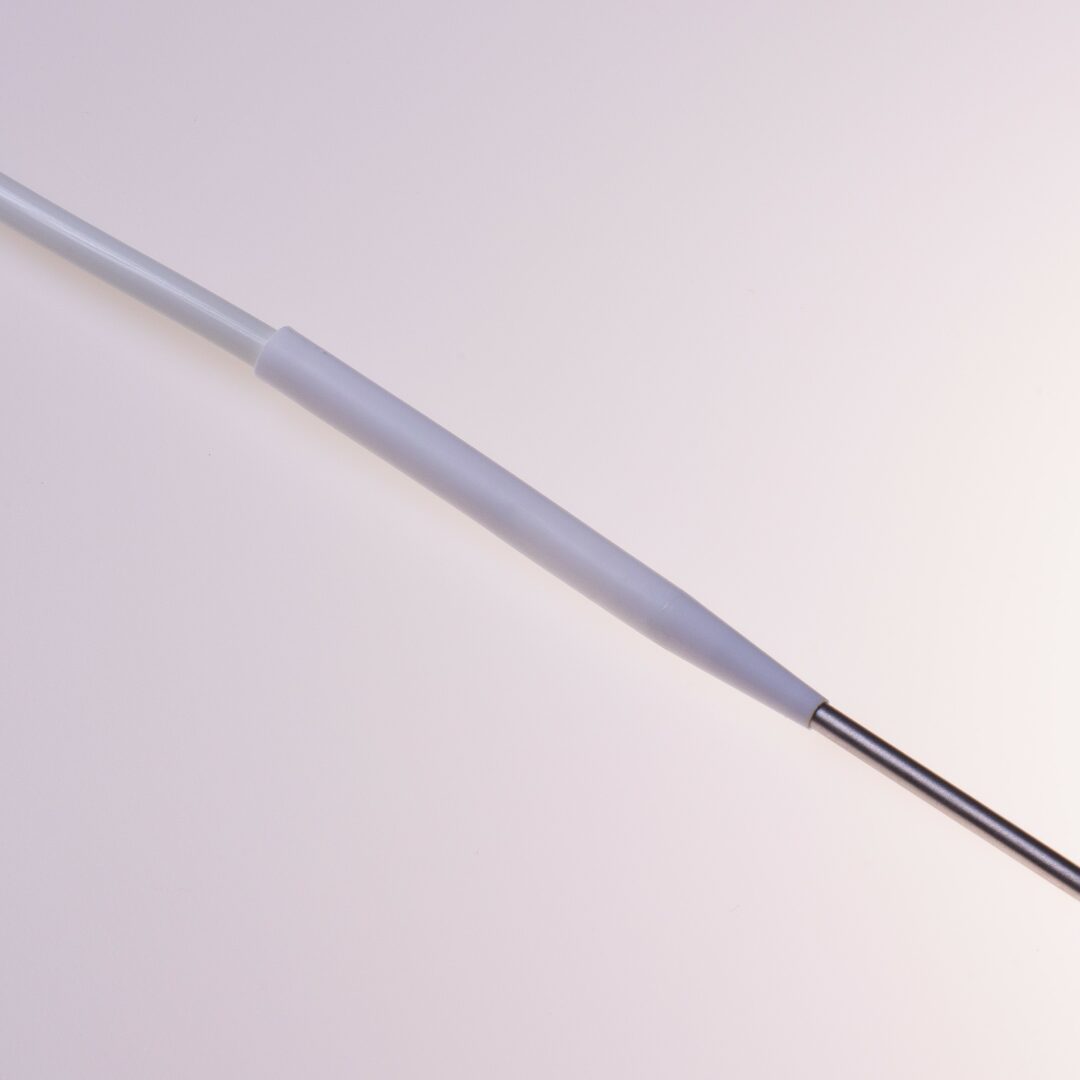

Der HFS Hemo Flow® ist ein untertunnelter Langzeitdialysekatheter für die chronische Hämodialyse. Er ermöglicht einen mehrjährigen, verlässlichen Gefäßzugang im Dialysebetrieb.

Produktbeschreibung

Der HFS Hemo Flow® ist ein untertunnelter Vorhofkatheter für die chronische Hämodialyse.

Der HFS Hemo Flow® wird antegrad untertunnelt. Die Einführung in das Gefäß erfolgt über eine Splitkanüle mit Schleuse.